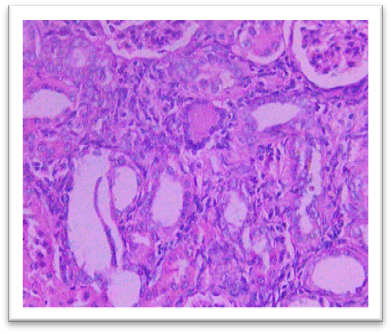

Histopathology

On day 42, rats were sacrificed for histopathological examination. Group I (Normal) and Group II (Lanthanum Carbonate only) showed normal kidney and liver architecture. Group III (Chronic Kidney Disease control) exhibited kidney damage, including crystals, congestion, haemorrhage, interstitial nephritis, and tubular dilatation. Group IV (Lanthanum Carbonate @150 mg/kg) showed moderate kidney fibrosis, mononuclear infiltration, and crystals. Group V (Lanthanum Carbonate @250 mg/kg) had mild fibrosis and sparse crystals. Group VI (Lanthanum Carbonate @500 mg/kg) showed minimal fibrosis and negligible crystals. Group VII (Lanthanum Carbonate @750 mg/kg) had minimal lesions with no crystals. Liver sections were normal in all groups. Histopathology studies revealed , The kidneys from a Chronic Kidney Disease (CKD) control rat (Group III) displayed significant macroscopic changes, including an increase in overall kidney size and the presence of multifocal, pinpoint, white granular raised lesions that were widely dispersed across the cortical surface. These observations are consistent with pathological alterations associated with CKD. Similar findings were reported by Yang et al. (2013) and Ali et al. (2015), who observed renal tissues exhibiting varying degrees of swelling and the presence of widespread white granular deposits on the cortical surfaces, consistent with the pathological features described in this study. Damment et al. (2011) observed significant changes in kidney architecture of Adenine induced Chronic Kidney Disease animals. The kidney from Group VII, treated with Lanthanum Carbonate @ 150mg/kg, 250mg/kg , 500mg/kg and 750 mg/kg body weight, demonstrated significant architectural improvement, along with a notable reduction in the number of crystalline deposits, indicating a substantial restoration of renal morphology and potential therapeutic efficacy at this dosage.

Fig. 19 Group III Kidney exhibits the crystals, congestion and haemorrhage. interstitial infiltration of mononuclear cells and fibrosis. Dilatation of the tubules, focal oedema, and focal interstitial nephritis under H & E 400X.